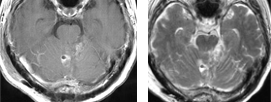

症例 4

腎臓癌による左前頭葉深部白質の転移性小脳腫瘍に対して開頭腫瘍摘出術を施行し全摘しました。脳浮腫の懸念がなくなったため術後ガンマナイフを併用しました。5年以上再発なく経過しています。

症例 5

腎臓癌による右側頭葉の転移性小脳腫瘍に対して開頭腫瘍摘出術を施行し全摘しました。術後ガンマナイフを併用しました。術前に視野障害を自覚しておりましたが、術後改善しました。腫瘍の全摘に加え、機能も回復しました。

腎臓癌の脳転移巣は腫瘍サイズが小さい割に脳浮腫が強い場合が多いです。写真で呈示した如く転移性脳腫瘍の肉眼所見は、血管奇形や血管腫と似ており正常脳との境界がわかりやすいため比較的摘出は容易です。また広範囲な脳浮腫も腫瘍を全摘すると消失します。